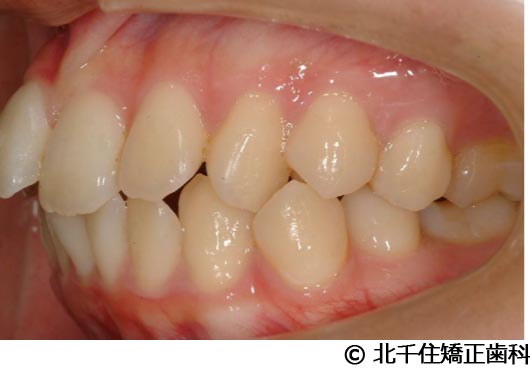

【症例2】上顎前突症

- 治療前

- 治療中

- 治療後

- 治療名

- 上顎前突症

- 費用

- 1,399,000円(税込)

- 期間

- 3年6ヵ月

- 治療回数

- 42回

- 通院頻度

- 1ヵ月ごと

- 年齢・性別

- 19歳10ヵ月・男性(初診時)

治療内容

-

患者様の症状

主訴:出っ歯、口元の突出、横顔をきれいにしたい

治療方法

骨格性の上顎前突、上下顎第一小臼歯4本及び上顎第二大臼歯を抜歯して矯正用アンカースクリューを併用してワイヤー矯正治療(セラミックブラケット)。

治療結果

骨格性上顎前突に対し、抜歯および矯正用アンカースクリューを併用した矯正治療により歯列および咬合関係の調整を行った症例である。治療後は保定装置を使用し、歯列および咬合の安定維持を目的として定期的な経過観察を行っている。

※治療結果は個人差があります。

治療を行う上での注意点(リスク・副作用)

歯磨き不良に伴うカリエスや歯周病、顎関節症、歯根吸収など。